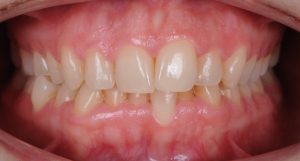

Maloclusión

Se caracteriza por una alineación incorrecta de los dientes, donde los dientes superiores e inferiores están en una relación normal, pero hay una falta de espacio que provoca que los dientes se solapen o estén apiñados.

Este problema puede generar dificultad para mantener una correcta higiene dental y afectar la estética de la sonrisa

INITIAL

22 Semanas de Tratamiento